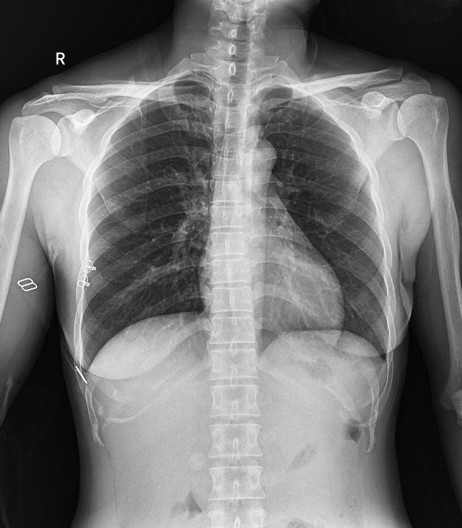

普利德醫(yī)療自主研發(fā)的新一代數(shù)字化X線透視攝影系統(tǒng),可應(yīng)用于DR攝影、數(shù)字透視、數(shù)字造影以及可視化精準(zhǔn)DR拍片等多種臨床X線檢查領(lǐng)域。

● 最高幀速可達(dá)30幀/秒,動(dòng)態(tài)采集清晰流暢,避免漏診、誤診情況的發(fā)生;

● 在可視過(guò)程或回放過(guò)程中,如發(fā)現(xiàn)疑似病灶,可進(jìn)行毫秒級(jí)高清點(diǎn)片,隨時(shí)抓取單幀圖像,精準(zhǔn)捕抓病灶。